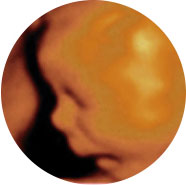

四维彩超能多方位、多角度、立体显示胎儿生长发育情况,为早期诊断胎儿先天性体表畸形如唇裂,脊柱裂,大脑、肾、心脏、骨骼发育不良等,和先天性心脏疾病提供全面的科学依据。

怎样选择排畸时间?| 仪器 | 美国E8四维 | 普通四维 |

| 画质 | 立体动态成像,画质比较清晰 | 动态成像画质普通 |

| 优势 | 多方位、角度地观察孕宝宝的生长发育,对孕妇潜藏的疾病进行检测,无辐射。 | 较准确地动态呈现腹中胎儿的生长发育情况 |